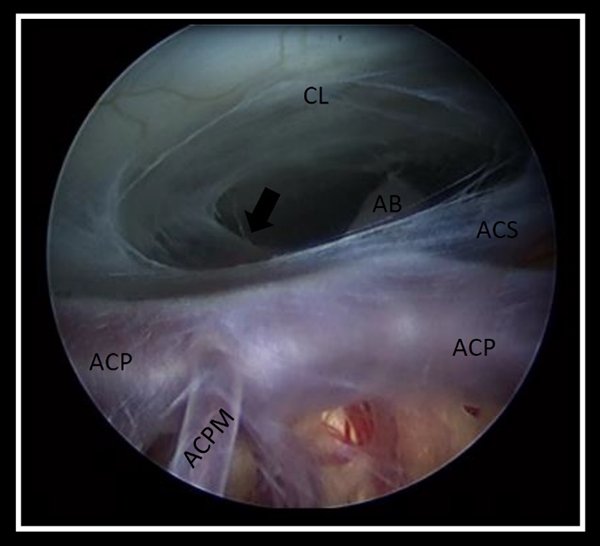

Como hallazgo intraquirúrgico, en 8 casos (62%) se constató el cierre completo de la ostomía, en 4 (30%) se observó el cierre de la ostomía por aracnoiditis, mientras que solo en 1 caso (7%) la ostomía permanecía permeable (Figura 2).

Figura 2. Imágenes intraquirúrgicas del piso del tercer ventrículo, donde se observan los hallazgos durante la Re-TVE. A) Ostomía cerrada íntegramente, no se observan rastros de la primera TVE, B) Ostomía cerrada con aracnoiditis, es posible observar los bordes libres de la ostomía (flecha) y la aracnoiditis en su interior (punta de flecha), C), ostomía permeable, se aprecian los bordes libres de la ostomía (fecha). III PC: tercer par craneal, AB: arteria basilar, CL: clivus, INF: infundíbulo, TM: tubérculos mamilares.